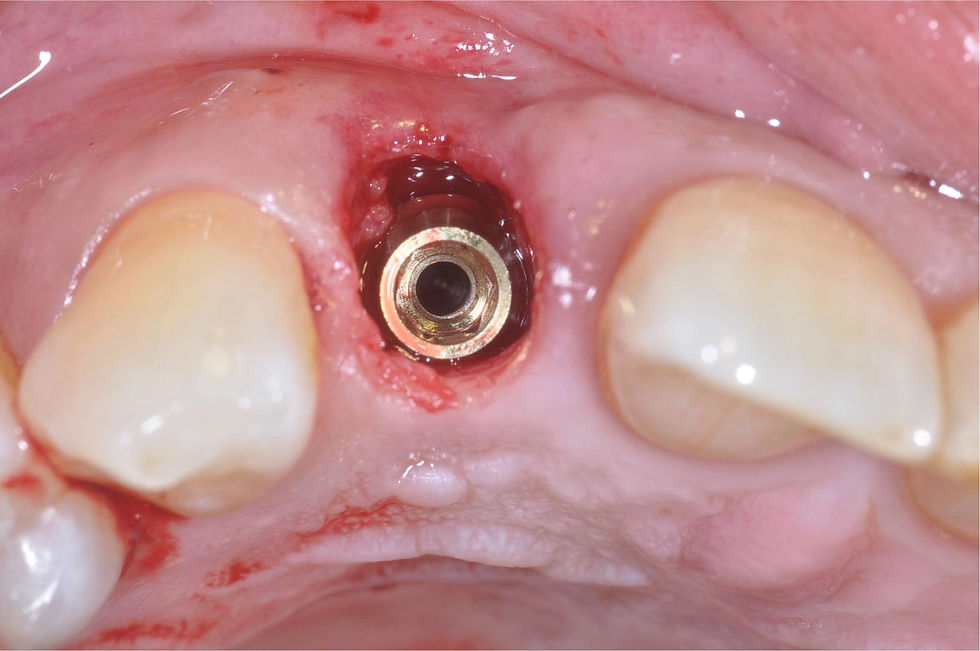

Insertion of the temporary PEEK abutment with titanium base, milled by the laboratory to obtain a feather edge morphology.

Relining and polishing of the temporary crown, whose morphology helps to stop the bleeding and consequently to stabilize the clot.